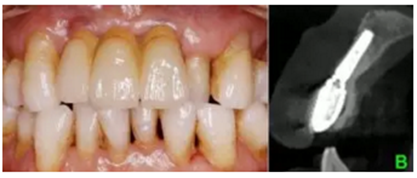

(4)3-shape數(shù)字化口掃進行數(shù)據(jù)采集及最終修復(fù)體制作

結(jié)合PRF的位點保存術(shù)后牙槽嵴輪廓豐滿,CBCT示骨量充足,數(shù)字化種植外科導(dǎo)板輔助下植體植入三維位置精確,種植體骨結(jié)合良好,數(shù)字化口掃系統(tǒng)數(shù)據(jù)采集高效、精確,臨時修復(fù)體戴入,軟組織成形,最終修復(fù)體戴入后穩(wěn)定、密合,牙齦軟組織色澤形態(tài)正常,美學(xué)效果良好。

數(shù)字化口腔掃描以其高效、快捷、精確、簡便、舒適性高等特點逐漸代替?zhèn)鹘y(tǒng)印模方式,數(shù)字印模無明顯盲區(qū)、三維形態(tài)精確、可靠性高,便于醫(yī)技遠程交流,制定最佳方案,減少了修復(fù)體返廠的風(fēng)險。數(shù)字印模的精確性也為最終修復(fù)體的長期密合性和穩(wěn)定性提供了保障。